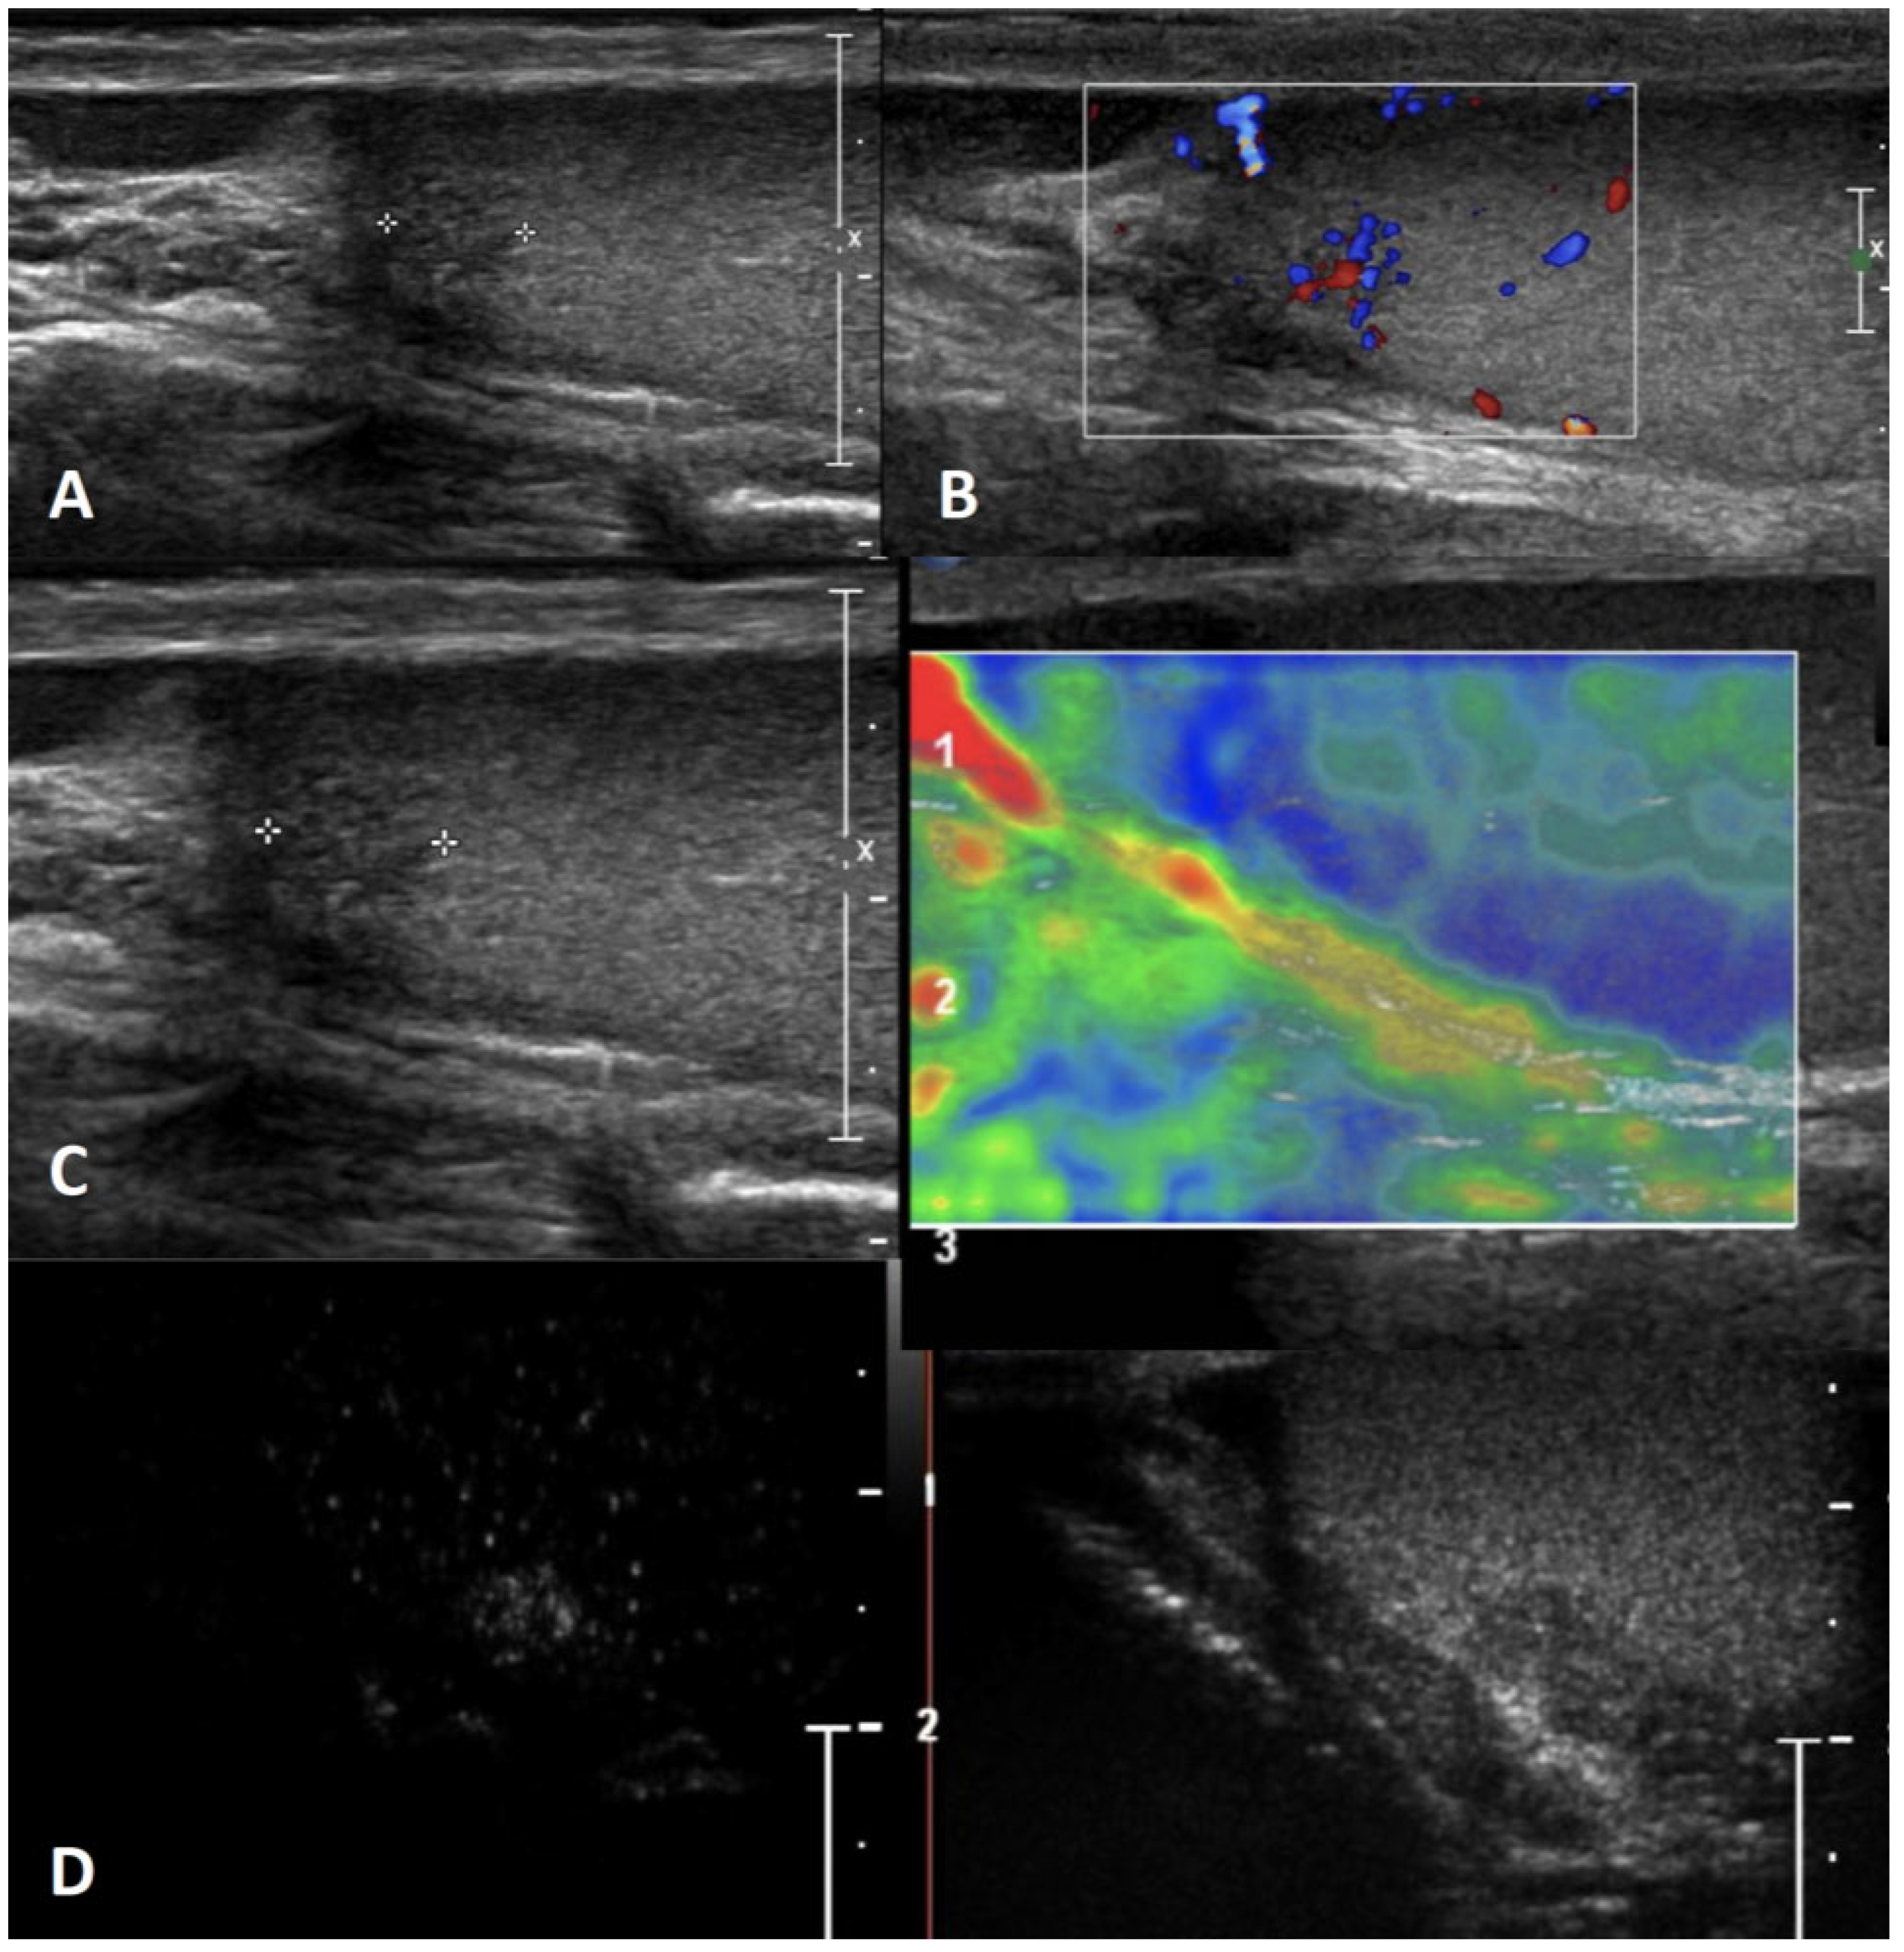

4.10. Infectious Granulomatous Orchitis

| Infectious (focal) granulomatous orchitis | Acute scrotal pain, testicular enlargement, fever; possible epididymal enlargement, scrotal wall thickening and hydrocele | Single or multiple variable echogenicity areas with blurred margins; appearance depends by the pathologic stages of infection, which include caseous necrosis, granulomas, and healing by fibrosis and calcification | Internal OR peripheral depending on the stage | Unenhanced/ perilesional rim enhancement OR hyperenhanced | Heterogeneous pattern of firmness depending on the stage |